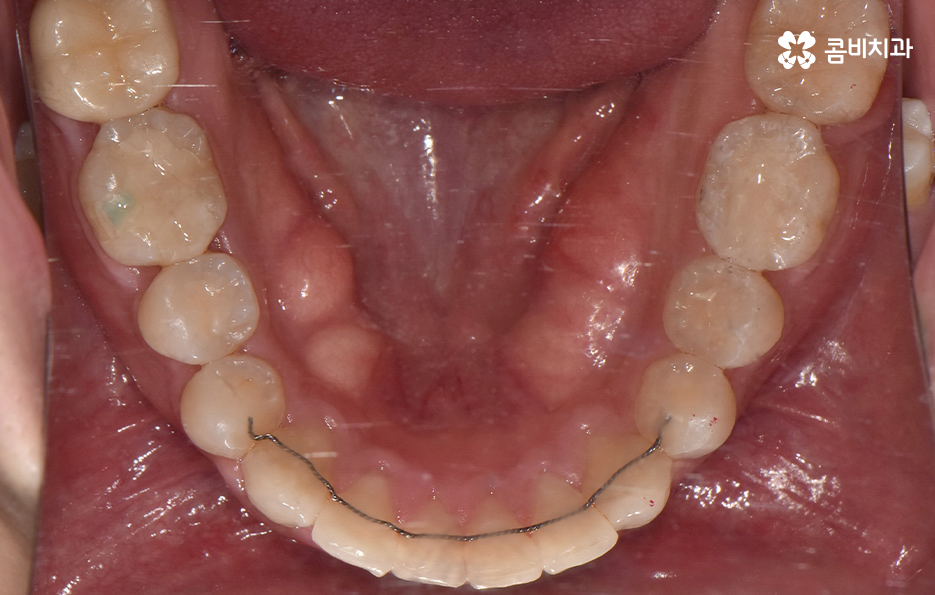

하지만 위에 보시는 환자분의 사례는 윗니와 아랫니의 교합을 고려하고 얼굴형, 골격 등을 고려했을 때도 아랫니만 교정이 가능했던 사례인데 일반적으로 윗니가 아랫니를 살짝 덮고 있어야 하는데 아랫니의 앞니 부분이 유독 안으로 들어와 있었기 때문에 아랫니교정 만으로도 치아교정이 가능했던 사례라고 보시면 좋을 거예요

위 환자분의 사례로 보면 아랫니 중에 하나가 유독 앞으로 튀어나와 있고 나머지 치아는 안으로 들어가 있기 때문에 교합으로 따져볼 때는 아랫니를 전체적으로 앞으로 이동시켜야 했기 때문에 비발치로도 충분히 교정이 가능했고 아랫니교정 만으로도 치료가 가능했어요

이처럼 치아교정의 계획은 각 환자분들에 따라서 천차만별로 달라지고 만약 비슷한 아랫니교정에 대한 고민을 하시는 분들이더라도 디테일한 치료 계획은 치열만이 아니라 골격과 얼굴형도 고려하여 세워야 하기 때문에 환자분들에 따라 전혀 다른 치료 계획이 세워질 수 있다는 점을 알아두시길 바라고 있어요